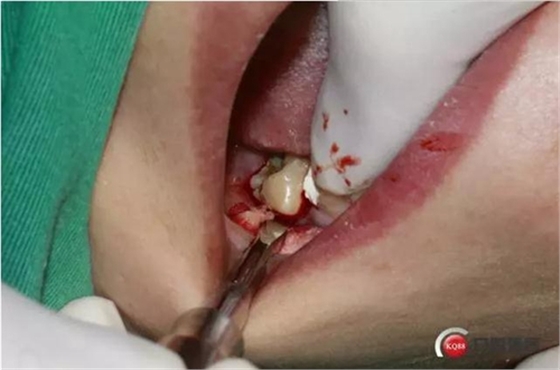

4%鹽酸阿替卡因腎上腺素局部麻醉,

口內(nèi)照片,48遠(yuǎn)中三分之一覆蓋部分牙齦。